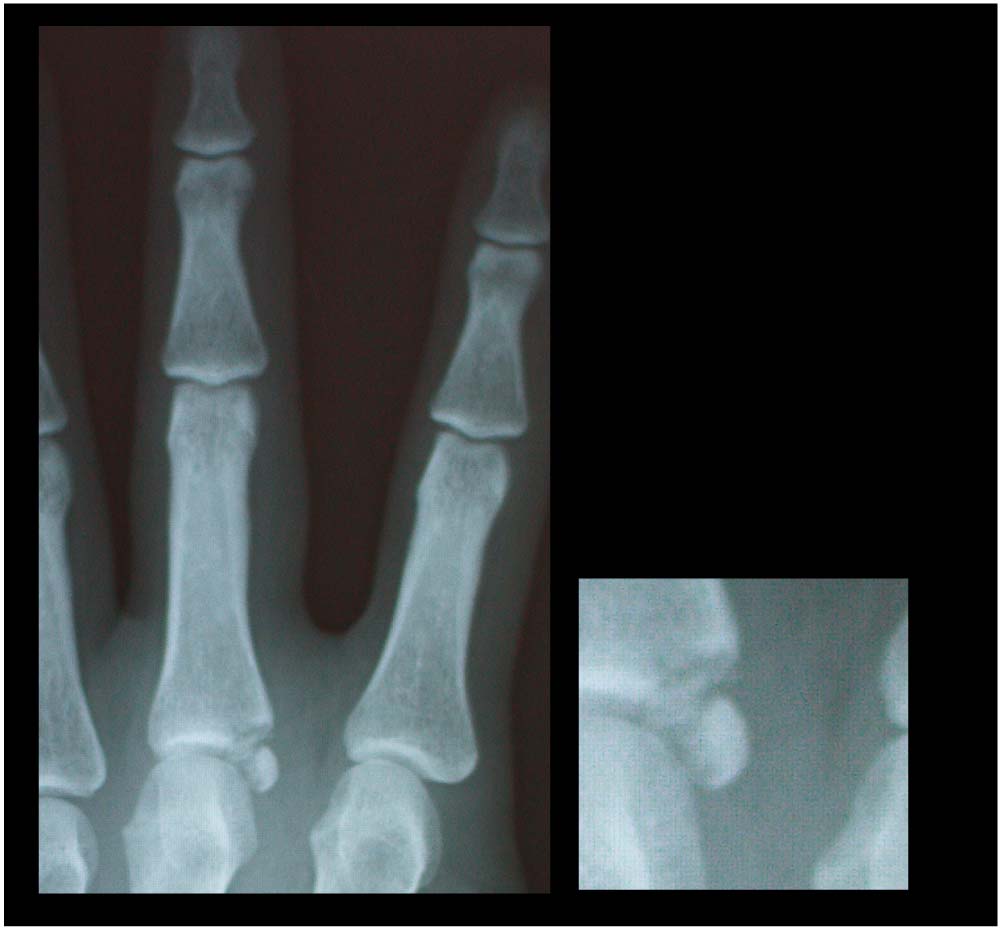

先日、地元のparkのフラットで、寒いからUPを しっかりやってたら、指から地面について指をグリッチョしてしまいました。。 グリッチョした時にポキッ??コキッ??とゆうような 音がしたんですが、指も動くので、大ジョブっしょと 思ってたんですが。。。どんどん腫れてきて。。 次の日の仕事は、左手、あまり使えなく。風邪もなおってないので、早退して病院へ

見事とは、いいづらいような微妙な。。わかりづらいので拡大!!

他の指と比べると何やら、丸い石ころのような物が。

これが 原因の骨が欠けたみたいな。。

なんちゃら骨折って言ってました。

これ、ほっといても 治るらしいんですが、この石ころみたいなのが肉の中で回転してる らしく

ほっといて、うまくつくかわからなく後遺症みたいになる可能性もあるかもと。。。言われたので来週から手術&入院してきます。。。